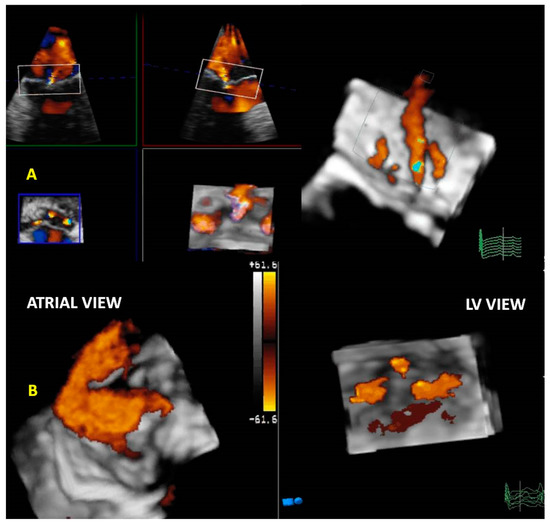

3.3. Quantification of Mitral Regurgitation